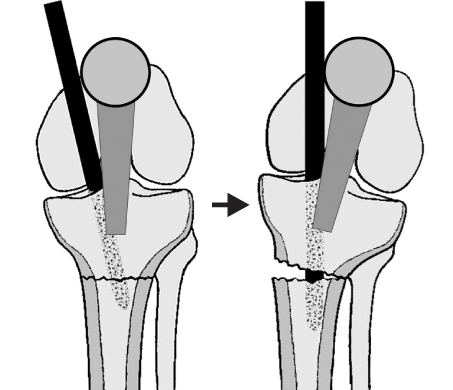

Fig. 3

Medial entry point and laterally directed insertion angle of the nail into the proximal fragment results in valgus malalignment as the nail engages into the distal fragment.

jkfs-22-197-g003.jpg

Fig. 4

Posteriorly directed insertion of the nail into the proximal fragment results in apex anterior angulation at the fracture site when the nail engages into the distal fragment.

Fig. 3 Medial entry point and laterally directed insertion angle of the nail into the proximal fragment results in valgus malalignment as the nail engages into the distal fragment.

Fig. 4 Posteriorly directed insertion of the nail into the proximal fragment results in apex anterior angulation at the fracture site when the nail engages into the distal fragment.